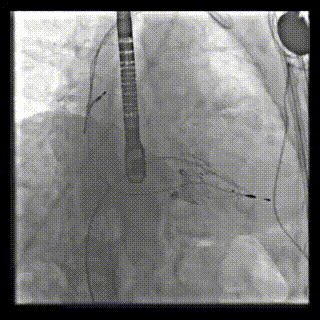

2021年12月24日,復(fù)旦大學(xué)附屬中山醫(yī)院葛均波院士團隊成功應(yīng)用LuX-Valve Plus為一例極重度三尖瓣反流(TR)合并房顫、房缺的患者完成了經(jīng)血管三尖瓣置換術(shù),這是在前基礎(chǔ)上,本周完成的第三例經(jīng)血管三尖瓣置換手術(shù),葛均波院士、周達新教授等與心外科魏來教授、賴顥教授,心超室的潘翠珍教授、李偉教授及麻醉科的郭克芳教授共同完成了本周手術(shù),均獲得圓滿成功!患者術(shù)后超聲顯示無TR,臨床癥狀明顯改善。本周手術(shù)的成功也為LuX-Valve Plus救治性臨床研究添上了濃墨重彩的一筆。

本周三例接受LuX-Valve Plus經(jīng)血管三尖瓣置換術(shù)的患者中,第一例患者為冠狀動脈旁路移植術(shù)+Bentall+二尖瓣成形術(shù)后;第二例患者為永久起搏器植入術(shù)后,存在跨三尖瓣導(dǎo)線;第三例患者合并房顫、房缺及左心耳封堵術(shù)后。

三例患者入院后,葛均波院士團隊周達新教授、潘文志教授、張源博士、陳莎莎博士及心超室的潘翠珍教授、李偉教授對患者的情況進行詳細評估和討論,最終決定為三例患者選擇LuX-Valve Plus40mm、50mm和50mm型號的瓣膜進行手術(shù)治療。手術(shù)后即刻拔除氣管插管,術(shù)后患者三尖瓣反流癥狀得到顯著改善,復(fù)查心超結(jié)果顯示人工三尖瓣瓣膜支架固定穩(wěn)定,瓣葉關(guān)閉形態(tài)未見異常,未見明顯反流。